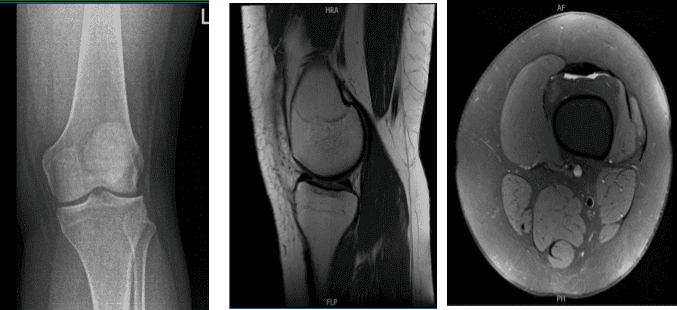

Her X-ray showed no significant degenerative changes and no acute fractures. We agreed to have an MRI which showed a bucket handle tear of the lateral meniscus.

MRI of the left knee